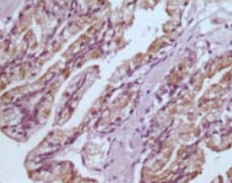

IHC    1/200 - 1/1000